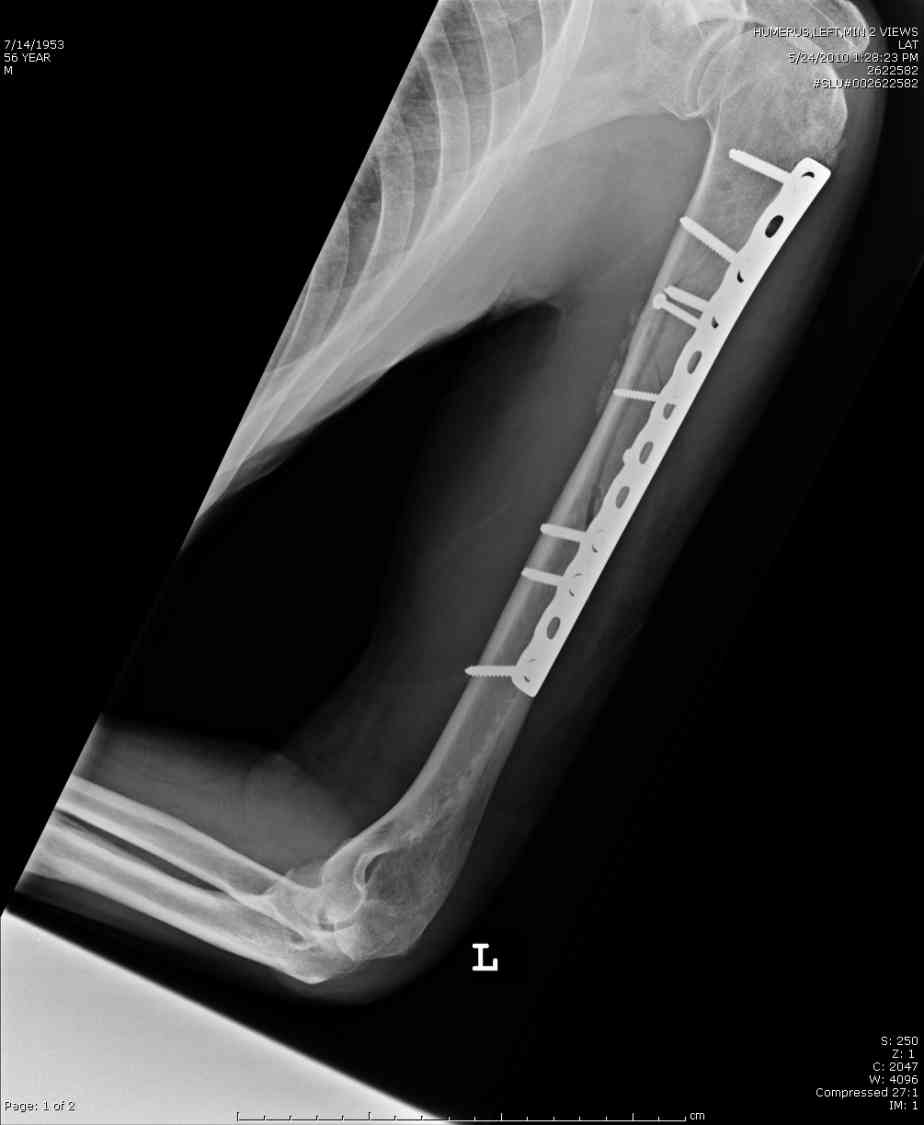

Здесь нет необходимости в серкляже. Вмешиваться на промежуточных отломках приходится, если есть угроза перфорации кожи, или промежуточный отломок попал в фасцию, как пуговица в петлю. В приложении сегментарный оскольчатый перелом плеча в проксимальном отделе, фиксированный больщеберцовым стержнем. Как видите, обошлось без серкляжа. Функция полная.

Пример отличный.

Вот что значит лечить перелом, а не рентгенограмму!

Александр, великолепные снимки! Вопрос - что за гвоздь?

Это укороченный большеберцовый стержень, которые делает предприятие "ЦИТО".

на синтезовский UTN похож))

Скажите пожалуйста, Александр Николаевич, почему Вы использовали большеберцовый гвоздь?

Доступные на тот момент гвозди для плеча имели худшие возможности фиксации в коротком проксимальном отломке.

Уважаемый Александр Николаевич! На продемонстрированных вами рентгенограммах имеется достаточно большое на мой взгляд смещение отломков после фиксации блокируемым гвоздем. На счет полной функции все понятно, а нет ли каких либо сосудистых расстройств конечности? Имею ввиду венозную недостаточность или лимфостаз.